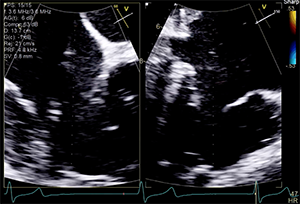

The patient’s left ventricular (LV) systolic function was mildly reduced (LV ejection fraction, 40%–45%), and he had a dilated right ventricle with mild systolic dysfunction based on standard normal ranges (Figure 1 and Figure 2). His right ventricular (RV) systolic pressure was estimated to be 56 mm Hg, as assessed by echocardiography. The results of right heart catheterization showed a pulmonary capillary wedge pressure of 19 mm Hg (V wave to 28 mm Hg), pulmonary artery pressure of 50/14 mm Hg (mean, 29 mm Hg), RV pressure of 50/14 mm Hg, and right atrial pressure of 15 mm Hg (V wave to 20 mm Hg).

Transthoracic and transesophageal echocardiography (TEE) confirmed severe functional TR due to annular dilation associated with RV and right atrial enlargement. Mild leaflet tethering, predominantly septal, was also appreciated. The coaptation gap was < 10 mm and the jet origin was predominantly central with extension toward the anteroseptal commissure. Image quality in both transesophageal midesophageal and transgastric windows were good (Videos 1–5).

An edge-to-edge device was selected due to the acceptable coaptation gap and expected good-quality procedural imaging for guidance. A single Pascal device was deployed between the anterior and septal leaflets to successfully repair this patient’s tricuspid valve. Postprocedure TR was mild to moderate, from a baseline of severe (or likely “massive” if using an expanded grading scheme). Independent leaflet grasping was utilized due to the mild relative tethering of the septal leaflet, which allowed optimization of leaflet insertion to ensure maximal effect and stability of the single device. There were no procedure-related complications.